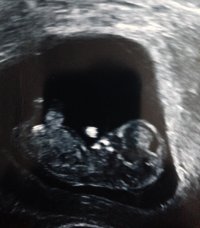

Merhaba nub çıkıntısına göre bebeğinizin cinsiyeti kız . Tabi nub teorisiyle cinsiyetin % 100 net sonuç vermediğini de belirtelim.. Doktorlar ileri haftalar da bile yanılabiliyor. 20. hafta ve sonrası bebeğin cinsiyeti net olarak belirlenebilir.

Aslında ilk olarak bu haftalarda erkek dediler şimdi kı dıolar kafam karıştı o yüzden sorayım dedim ikinci çocuk ilk kız olunca sağlıklı olsunda yinede erkek bekleniyor teşekkür ederim